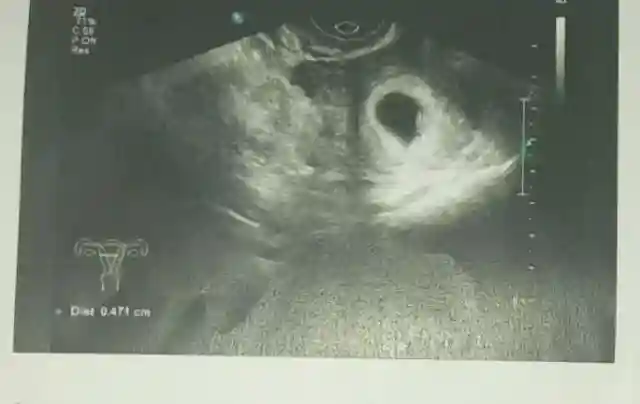

1、B超监测胚胎,胎儿发育,≥6周时没有妊娠囊

2、有妊娠囊但出现变形皱缩,在妊娠囊≥4cm,但却看不到胎芽

3、胎芽的头臂长度≥1.5cm,但却没有胎心搏动

出现以上3种情况,基本上可以断定为胎儿发育异常,可判断为胎停育。